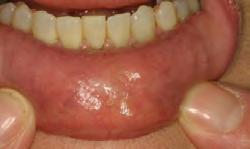

MICROLEAKAGE

PROVISIONAL REMOVED STAINING

2. Upon removing some of the composite, the extent of leakage is more evident. Contamination has occurred, therefore compromising the seal. Hemostatic, blood, sulcular fluid, saliva, and byproducts from anerobic bacteria can be sources of contamination. Retreatment is necessary.

1. For restorations, Astingedent™ X hemostatic and Ultrapak cord are ideal for controlling blood and sulcular fluids and can also protect tissue from burs. Use a firm air/water spray to remove excess hemostatic solution.